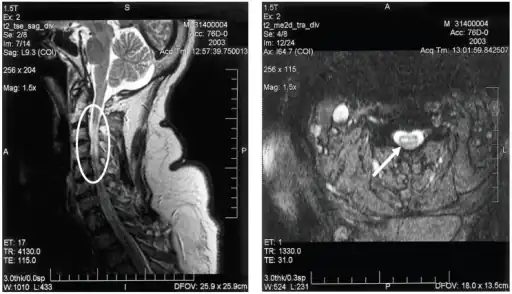

a,b)MRI of cervical spinal cord of individual with bilateral upper extremity paralysis and respiratory failure from West Nile poliomyelitis